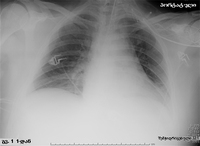

HAP-ის მქონე პაციენტის პორტატიული რენტგენოგრაფია. ყურადღება მიაქციეთ, რომ მარცხენა დიაფრაგმის თაღი არამკაფიოა მარცხენა ქვედა წილის დაჩრდილვის გამო და გულის საზღვარი ასევე არამკაფიოა მარცხენა ზედა წილის და ენისებრი სეგმენტის დაჩრდილვის გამო.

თანხმობა მიღებულია ლუისვილის უნივერსიტეტში, ლუისვილი, კენტუკი